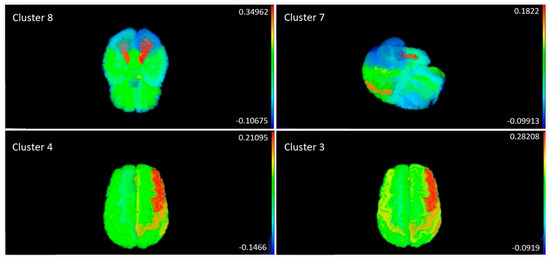

5.5.1. Clustering of Metabolites

5.5.3. Correlation Analysis—Mapping